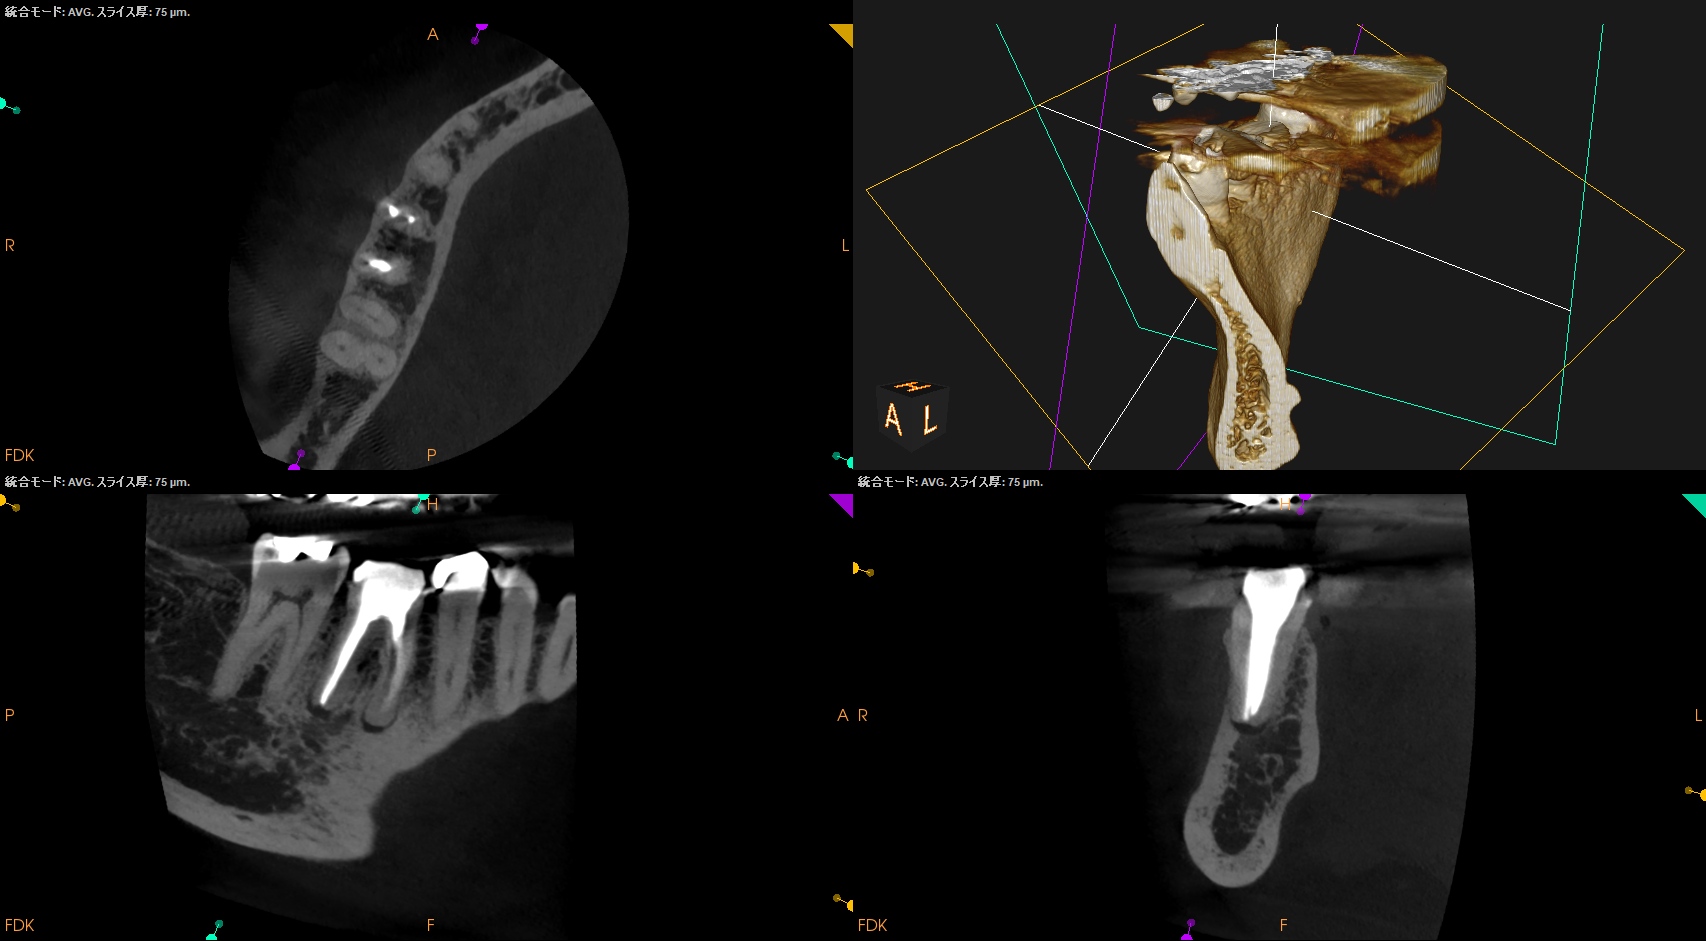

PA(2025.10.15)

CBCT(2025.10.15)

#30 MB

#30 ML

#30 D